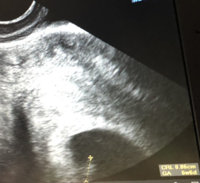

Täällä sama LA ja myös ensimmäinen raskaus! On kyllä jännät paikat! Mullakaan ei pahemmin oireita ole tällä hetkellä, paitsi väsymys! Joinakin päivinä tulee enemmän pikkusia oireita, mutta suurimmaksi osaksi ei tunnu missään! Tosin viikot 3-4 meni tuskaisten kipujen kanssa kärsien, niin oireettomuus on ihan hyvä juttu mulle! Eilen oli varhaisultra ja kaikki hyvin, niin nyt uskaltaa enemmän nauttia!Hei, jospa minäkin uskaltaisin liittyä tänne. Sitä kaipaa vähän seuraa tämän vielä salaisen uuden ja vähän yllättävänkin jutun kanssa.

Oi kun ihanaa! Itse yritin ottaa selvää varhaisultra mahdollisuuksista tässä lähialueella, joko tuossa lähikaupungissa on ehkä vain terveystalolla siihen kallis mahdollisuus tai pitäisi ajaa liki parinsadan kilometrin päähän... Vielä ei oikein uskalla kysellä julkisesti keneltäkään tutulta onko kukaan käynyt ja missä.Eilen oli varhaisultra ja kaikki hyvin, niin nyt uskaltaa enemmän nauttia!